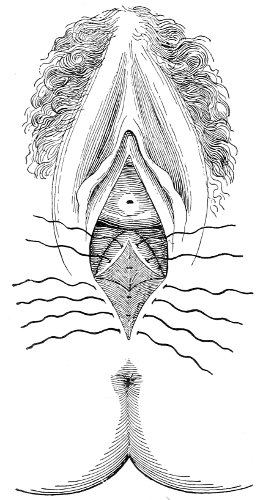

If the laceration extends up the posterior vaginal wall, two sets of sutures must be introduced—one on the vaginal aspect of the tear, and one on the skin aspect (Fig. 35).